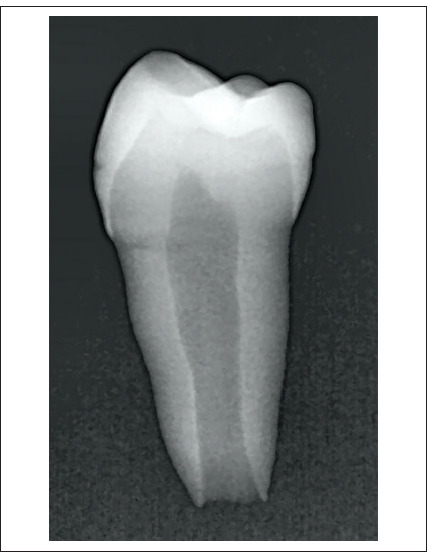

Methods: An impression was captured from the immature premolar root canal, followed by scanning and the subsequent design of prefabricated root canal models for immature permanent teeth (PRCMs). A total of forty PRCM replicas were precision-printed using advanced 3D printing technology. Subsequently, etch PRCM underwent meticulous filling with BioCeramic putty and a fibre post. After two hours, the fibre posts were removed and treated with hydrofluoric acid for all groups. Subsequently, fibre posts of groups except the GIC group received silane solution application. The PRCMs were categorised into four groups based on the cementation system employed: TC Group (n=10), SC Group (n=10), SCB Group (n=10), and GIC Group (n=10). After 48 h, the specimens underwent pull-out strength testing using a universal testing machine, performed along an axis parallel to the longitudinal axis of the fibre post at a crosshead speed of 1 mm/min. Failure modes were scrutinised using a stereomicroscope. The acquired data were subjected to robust statistical analyses, employing one-way ANOVA and Tukey HSD tests with a significance level set at α=0.05.